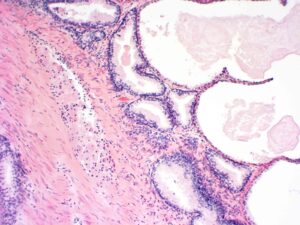

Das Ergebnis der Prostatabiopsie

Die Empfehlung des Urologen, eine Gewebeprobe (Biopsie) aus der Prostata zu entnehmen, basiert nicht auf einem Bauchgefühl, sondern auf klar definierten medizinischen Voraussetzungen. Diese Voraussetzungen wurden von Experten der an Diagnostik und Behandlung des Tumors